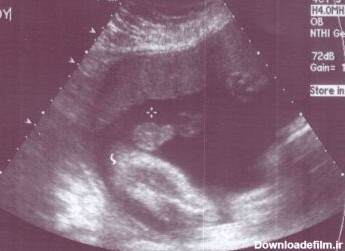

تصاویر سونوگرافی گاهی گیج کننده است. در اینجا گالری از عکس های واضح سونوگرافی جنین پسر در اختیار شما قرار میگیرد.

در عکس جنین در هفته دهم بارداری/ تصویر جنین در هفته دهم بارداری، جنین نمای کلی یک انسان کوچک را پید کرده و اندام های او قابل تشخیص اند ولی جنسیت جنین نه